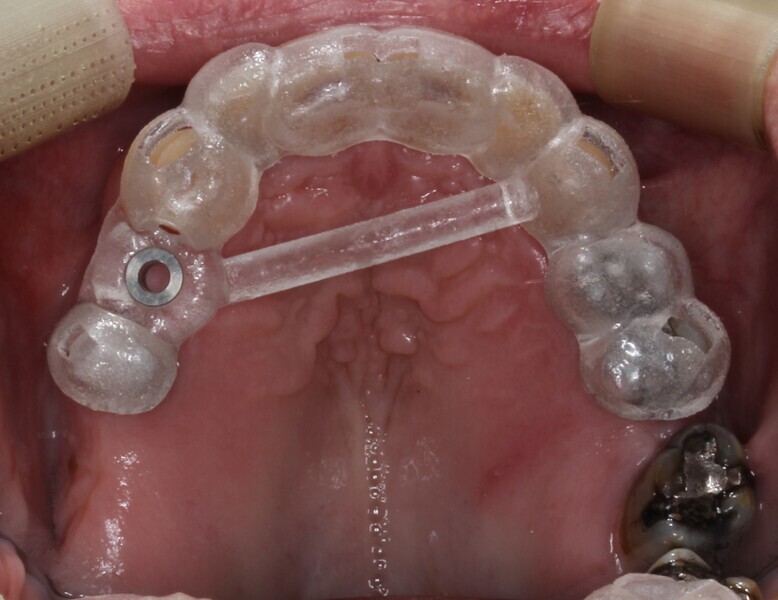

A tissue-level matrix implant (4.1 × 8.0 mm; TRI Dental Implants) was digitally positioned in order to design the surgical guide, based on parameters already preloaded on the extensive 3Shape Implant Studio library. A pilot guide was designed in this case, as it has been shown to produce similarly accurate results in comparison with fully guided systems.2 The surgical guide was printed out of V-Print SG (VOCO) on the MAX UV (Asiga) in 50 μm layers and was autoclaved after complete processing.

Based on the implant plan, a two-piece provisional restoration was designed using the same software (Figs. 6 & 7). The abutment portion would be printed in a clear splint material (KeySplint Hard, Keystone Industries) and highly polished for optimum transparency. This would allow for visibility of the healing process. To reduce the amount of polishing required, the abutment would be printed in 50 μm layers to diminish the appearance of the layers and using the UltraGLOSS material tray (Asiga; Fig. 8).

A separate facial veneer would be bonded to this abutment and would be printed in a restorative resin (saremco print CROWNTEC, SAREMCO Dental) to satisfy the aesthetic concerns of the patient. Two retentive slots would be incorporated into the abutment and veneer to ensure proper fixation during the bonding process (Figs. 9–11). Prior to final polymerisation in the Otoflash G171 (two 2,000 flashes; NK-Optik), the two pieces would be bonded together using the splint resin as a cementing agent (Figs. 12–14).